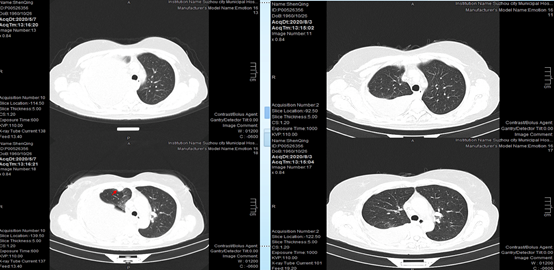

2020-01-16,CT复查提示患者胸膜处结节较前缩小,右下肺病灶较前缩小。

2020-03-23,患者再次复查CT,发现胸膜下结节较前增大,右下肺病灶继续缩小,但患者胸腔积液明显增多,疗效评估疾病进展(PD)。

头颅增强MRI没有发现头部转移灶,疗效评价疾病稳定(SD)。